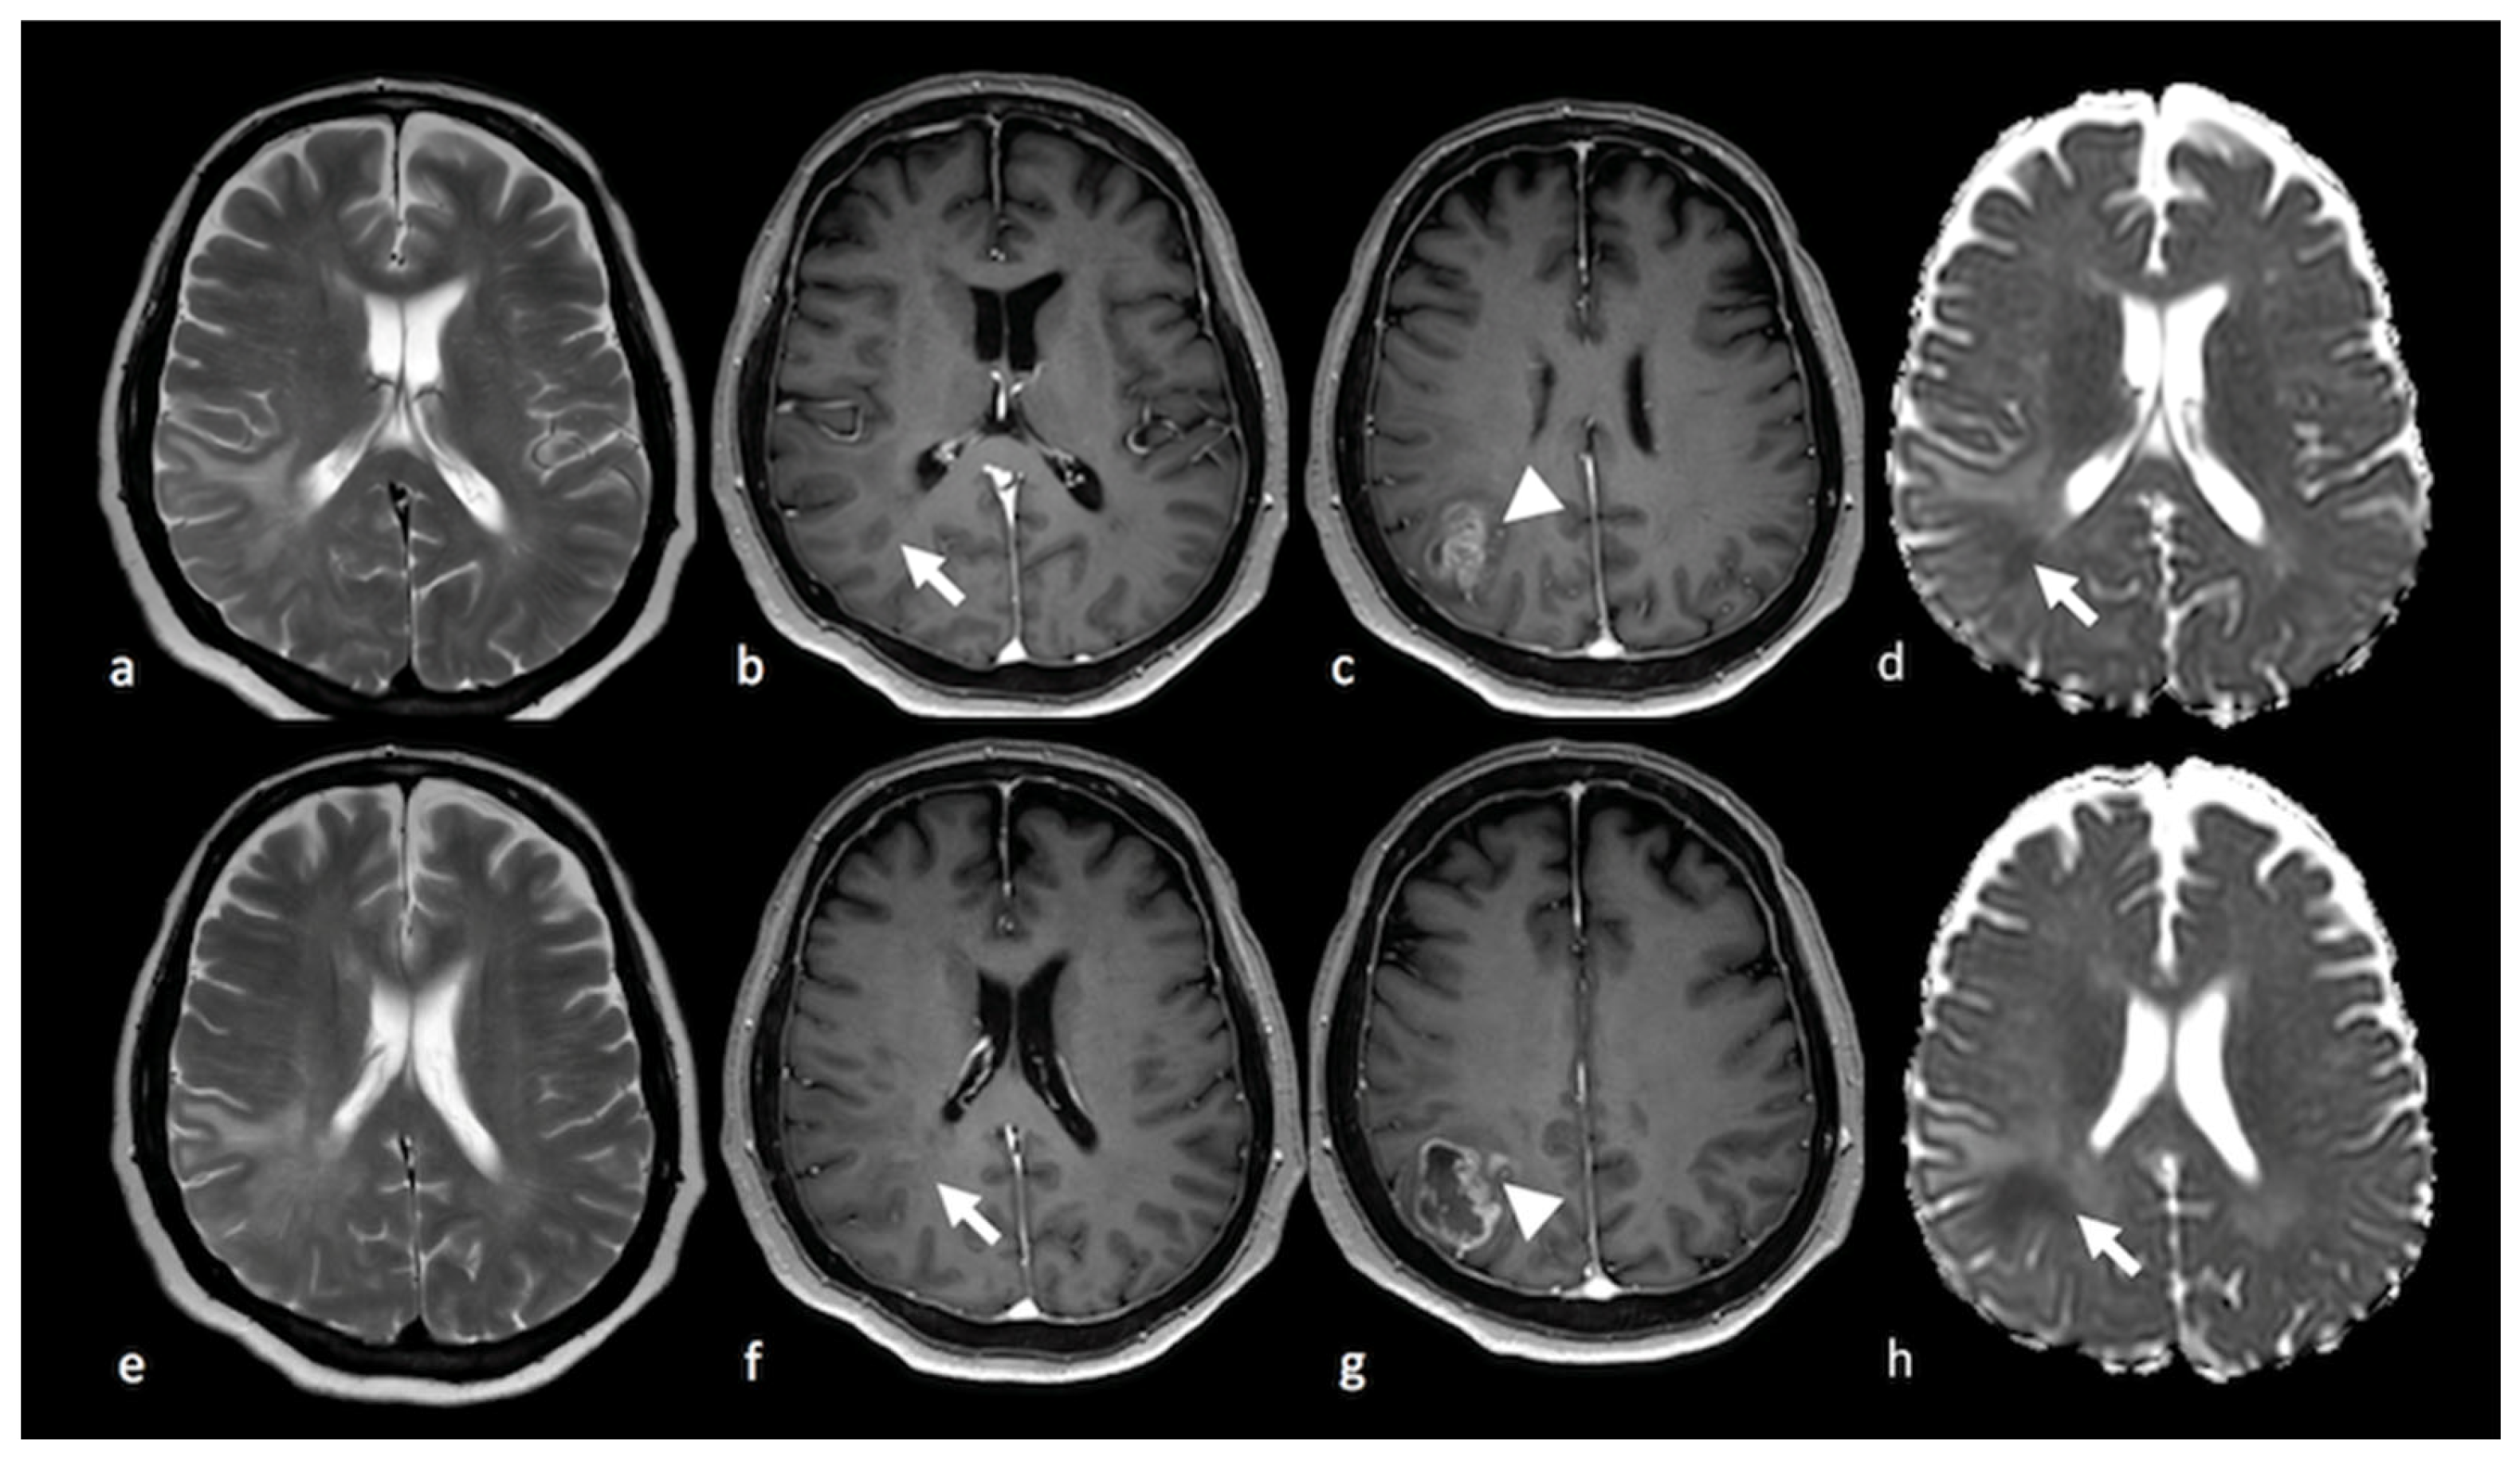

3.2.2. Diffusion Tensor Imaging (DTI)

3.2.3. Diffusion Kurtosis Imaging (DKI)

- Lee, E.J.; Ahn, K.J.; Lee, E.K.; Lee, Y.S.; Kim, D.B. Potential role of advanced MRI techniques for the peritumoural region in differentiating glioblastoma multiforme and solitary metastatic lesions. Clin. Radiol. 2013, 68, e689–e697. [Google Scholar] [CrossRef]

- Byrnes, T.J.; Barrick, T.R.; Bell, B.A.; Clark, C.A. Diffusion tensor imaging discriminates between glioblastoma and cerebral metastases in vivo. NMR Biomed. 2011, 24, 54–60. [Google Scholar] [CrossRef] [PubMed]

- Sternberg, E.J.; Lipton, M.L.; Burns, J. Utility of diffusion tensor imaging in evaluation of the peritumoral region in patients with primary and metastatic brain tumors. AJNR Am. J. Neuroradiol. 2014, 35, 439–444. [Google Scholar] [CrossRef]